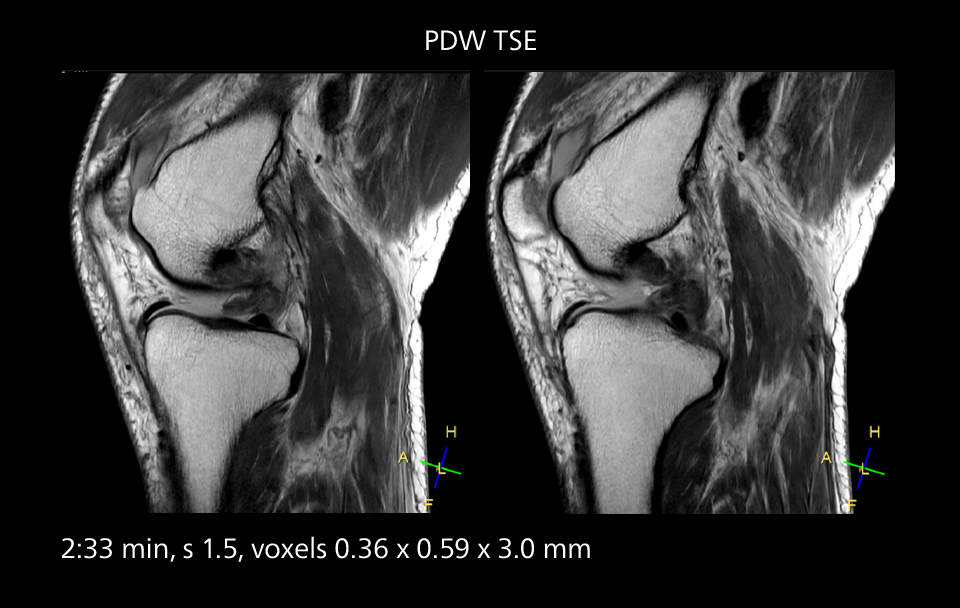

These images of an old cerebral infarction demonstrate the speed and image quality after upgrading to Elition X.

Crisp images are obtained with high resolution and short scan times using Elition X. A cyst can be seen.